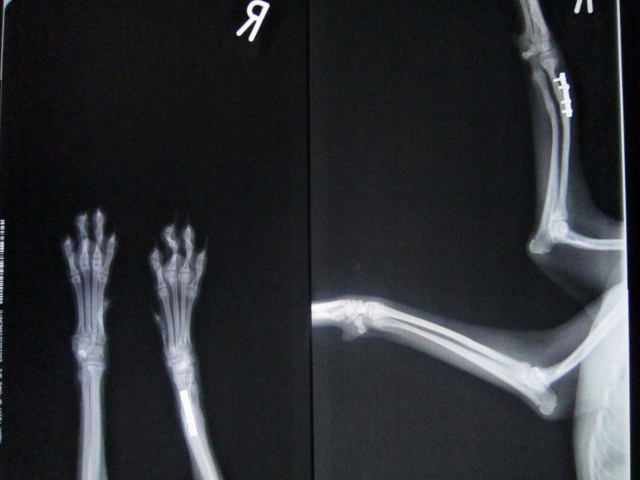

51日目のレントゲンです。

少しネジがゆるんでいますが、

骨癒合は良好です。

この後、抜プレートを行いました。